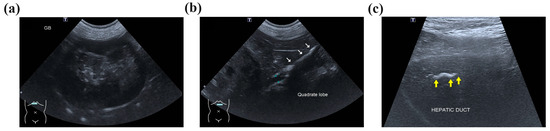

The dilated hepatic duct was packed off with wet gauze, and an incision was made on the most dilated section of the intrahepatic duct, which was the proximal aspect of the largest gallstone. The incision was performed 5 mm parallel to the intrahepatic duct’s longitudinal axis (Figure 3a). When the intrahepatic duct was incised, the tied suture knot was raised to create tension from the bottom of the left lateral hepatic duct to the top to prevent gallstones from passing into the hepatic duct of the left lateral liver lobe. Immediately after the incision of the hepatic duct, the largest gallstone was removed using vascular DeBakey thumb tissue forceps, and then, the hepatic duct was flushed and suctioned using a 5 to 6 Fr feeding tube and a 0.35 Fr Tomcat catheter with the guide removed. After removal of the intrahepatic cholelithiasis and bile, the hepatic duct was apposed with simple continuous 5-0 monofilament absorbable (polyglyconate) sutures (Figure 3b). Two gallstones in the CBD were removed by retrograde flushing into the GB using duodenal enterotomy, and a cholecystectomy was performed. After confirming hemostasis and no bile leakage from the surgical site, the abdominal cavity was flushed with warm 0.9% normal saline, and the abdominal wall and skin were closed.

Figure 3. Incision and closure of the intrahepatic bile duct. (a) Intrahepatic bile duct obstruction by the largest gallstone occurred after the site of the intrahepatic duct of the left medial liver lobe (LML) and left lateral liver lobe (LLL) was anastomosed. The diameter of the largest gallstone was approximately 7 mm on the CT scan, and it was confirmed to be the same size after surgery. A 5 mm incision was made in the proximal part of the gallstone. (b) After flushing the intrahepatic bile duct to remove the gallstones, the incision was closed with a simple continuous 5-0 absorbable suture (white arrow). No gallstones were identified near the common bile duct (CBD) or cystic duct (CD) at the left hepatic duct confluence.